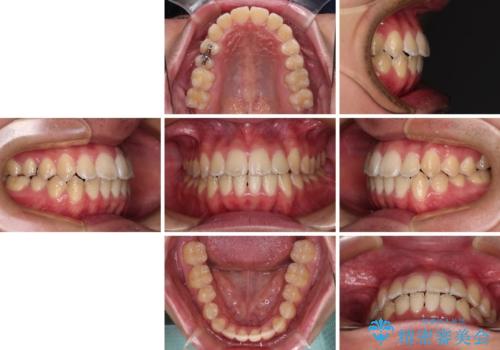

当初予定通り、1年間で治療を終えることができました。

- 上下前歯のデコボコを気にして来院された患者様です。

ワイヤー矯正でもマウスピース矯正でも可能でしたが、短期間で、自身の手を煩わせることなく治療を行いたいとのことで、ワイヤー装置にて矯正治療を行うこととしました。